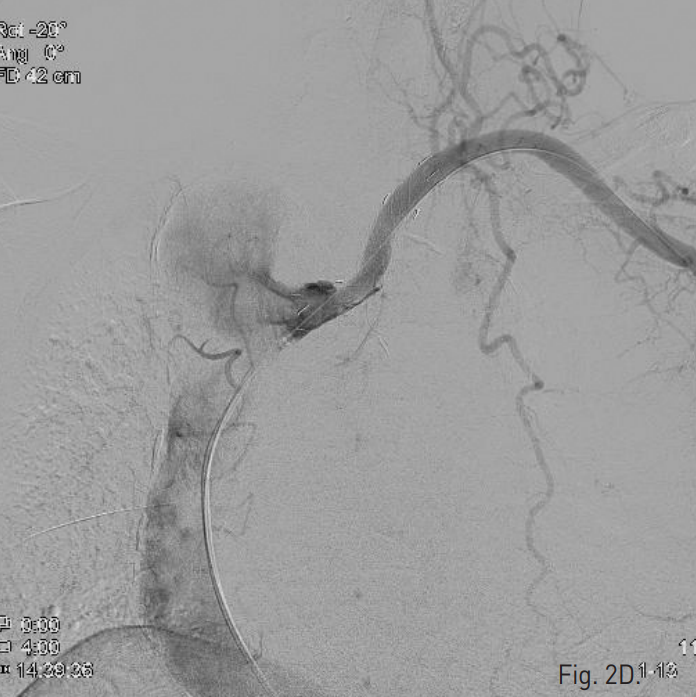

Endovascular repair 시술 후 1년 6개월 뒤 증상없이 추적검사로 시행한 조영증강 흉부 CT에서 aberrant left subclavian artery에 삽입한 stent-graft의 내강에서 aneurysm sac로 나가는 endoleak이 발견됨 (Fig. 1). Aneurysm sac의 크기는 변화 없었음.

Fig. 1

Contrast-enhanced axial CT scan shows the stent graft along the aberrant left subclavian artery. A large aneurysm with mural thrombosis is noted at the anterolateral aspect of the stent-graft, suggesting endoleak.